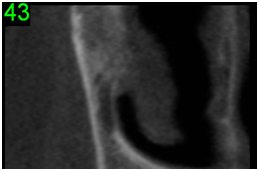

No canto superior esquerdo desses cortes individualizados aparece um número verde. Ele corresponde a região na escala milimetrada da imagem guia onde foi efetuado o corte tomográfico.

Corte tomográfico transversal oblíquo (imagem individual)